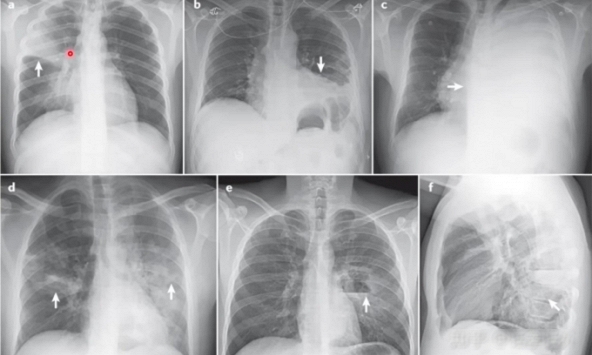

| Hít phải xịt chống nắng có thể gây phổi trắng - viêm phổi quá mẫn cấp tính nguy hiểm (Ảnh minh họa) |

Sau khi khám bệnh, chụp X-quang ngực của Hân Hân thấy nhiều mảng bóng lớn ở cả hai phổi, phổi gần hư chuyển sang màu trắng xóa. Xét nghiệm máu chỉ ra bạch cầu tăng cao và protein phản ứng C bình thường. Dựa trên bệnh sử và biểu hiện lâm sàng, bác sĩ kết luận cô bé bị viêm phổi quá mẫn cấp tính do hít phải xịt chống nắng. Cụ thể, cô bé phạm phải sai lầm mà không ít người mắc khi dùng xịt chống nắng: xịt thẳng vào mặt và há miệng dẫn tới nuốt phải các hóa chất.